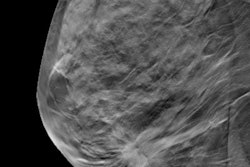

Digital mammography and later digital breast tomosynthesis (DBT) have been replacing film-screen mammography over the last several decades. However, it has not been established if these technological advances have significantly improved diagnostic performance.

"Digital breast tomosynthesis (DBT) is a technological advance that is still based in digital mammography. Improvements in cancer detection are likely related to being able to focus on a plane of tissue in a breast; removing tissue above and below that might obscure a cancer," Lee wrote. "DBT can also reduce 'false-alarms' from overlapping tissue that mimics a breast cancer. However, some limitations of digital mammography may still persist with DBT technology."